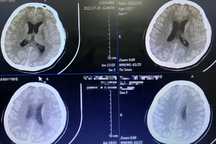

"Ca bệnh này gần giống như ca đột quỵ não nhưng nặng hơn rất nhiều. Nếu đột quỵ não chỉ gây tổn thương nhỏ ở một số vị trí thì ở trường hợp này là tổn thương gần như toàn bộ não. Chưa kể tình trạng suy tim nặng, suy thận, tổn thương gan", TS Nguyên thông tin.

Hình ảnh chụp não bị tổn thương của bệnh nhân.